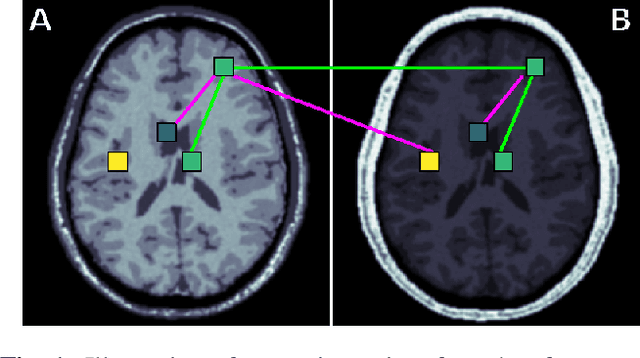

Abstract:Generalization of voxelwise classifiers is hampered by differences between MRI-scanners, e.g. different acquisition protocols and field strengths. To address this limitation, we propose a Siamese neural network (MRAI-NET) that extracts acquisition-invariant feature vectors. These can consequently be used by task-specific methods, such as voxelwise classifiers for tissue segmentation. MRAI-NET is tested on both simulated and real patient data. Experiments show that MRAI-NET outperforms voxelwise classifiers trained on the source or target scanner data when a small number of labeled samples is available.